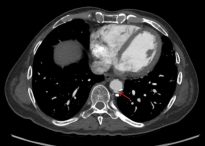

Penetrating aortic ulcers are usually an incidental finding on CT or MR. On CT look for contrast that is separate from the main aorta channel. An ulcer is sometimes hard to distinguish from an ulcerated plaque. An ulcerated plaque is actually not considered part of the “acute aortic syndrome” spectrum (it is more in line with a “regular” atherosclerotic process. I recommend reviewing images with vascular radiology. Doing so has helped me in the past. One differentiator is if contrast goes beyond the diameter of the aorta. Contrast outside the diameter denotes an ulcer (so, yes, the example in the picture below is not a perfect one):